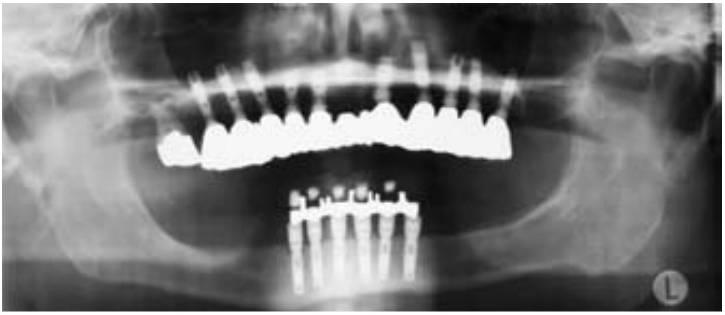

Los pacientes completamente edéntulos deben ser tratados con una sobredentadura removible o una prótesis fija. En cualquiera de los enfoques, la pérdida ósea debida a la pérdida del diente y los métodos para reducir la pérdida ósea futura forman parte de la planificación del tratamiento. Prácticamente todos los pacientes deberían llevar con el tiempo una restauración completamente implantosoportada (cap. 5).

Una mandíbula edéntula puede dividirse en tres secciones desde un punto de vista biomecánico: la anterior (de canino a canino) y las regiones posteriores bilaterales (premolares y molares). Una posición clave para los implantes consiste en un implante en cada región, al menos tres implantes claves.

Un maxilar edéntulo puede dividirse en cinco secciones: la región anterior (laterales y centrales), los caninos bilaterales, y la región bilateral posterior (premolar y molar). Una posición clave para los implantes consiste en un implante en cada región, o al menos cinco implantes claves.

El estrés global sobre todo el sistema del implante puede reducirse aumentando el área sobre la que está aplicada la fuerza. El método más efectivo para aumentar el área de la superficie de soporte del implante consiste en aumentar el número de implantes de soporte de la prótesis (fig. 4-32). Por ejemplo, estudios previos de Bidez y Misch han demostrado que la fuerza distribuida sobre tres pilares da como resultado un estrés menos localizado en la cresta del hueso que con dos pilares. Este estudio se aplica únicamente a los implantes que están ferulizados conjuntamente. De ahí que, cuando las fuerzas están aumentadas, debería reducirse el número de pónticos y aumentar el de pilares de implantes, en comparación con la planificación de tratamiento para un paciente ideal con factores de fuerza mínimos.